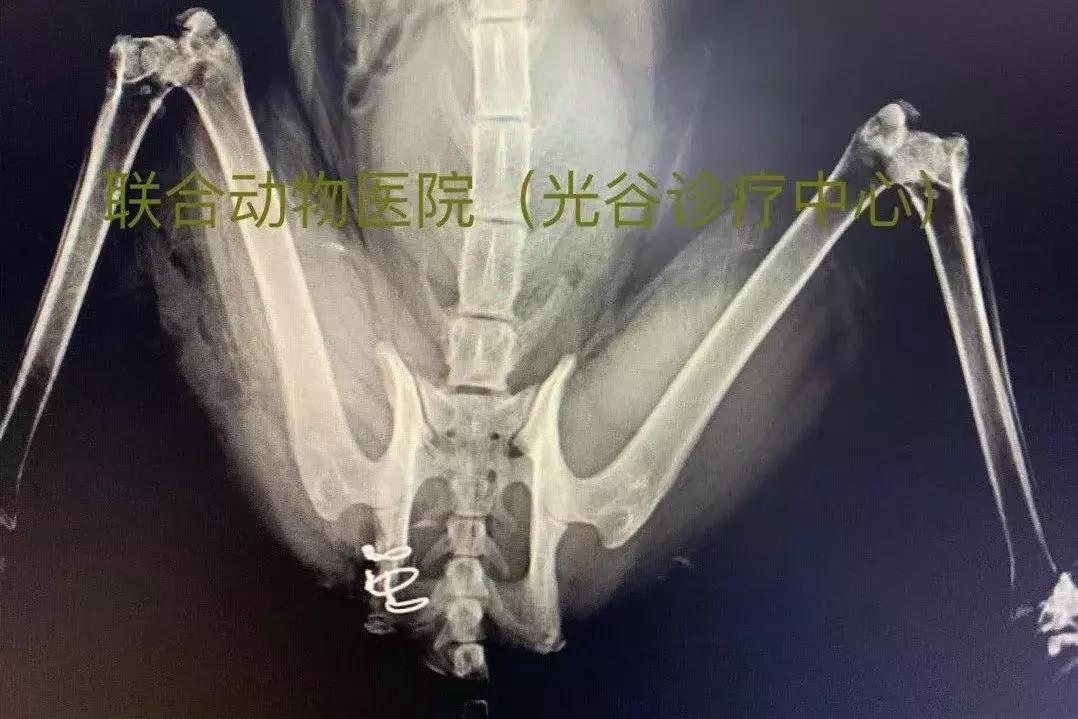

布偶二筒从七楼摔下,屁股被晾衣架戳出一个洞,强大的冲击力把坐骨直接折断成三块,坐骨结节完全游离。

坐骨下方碎片与坐骨棘能够连接处仅剩1毫米左右宽度,勉强拼出闭孔形状却无处固定。

最后只能先拼凑出后方骨块,再通过后方坐骨结节强大的骨皮质与闭孔前端坐骨棘连接,术后非常漂亮,与正常侧基本完全对称。